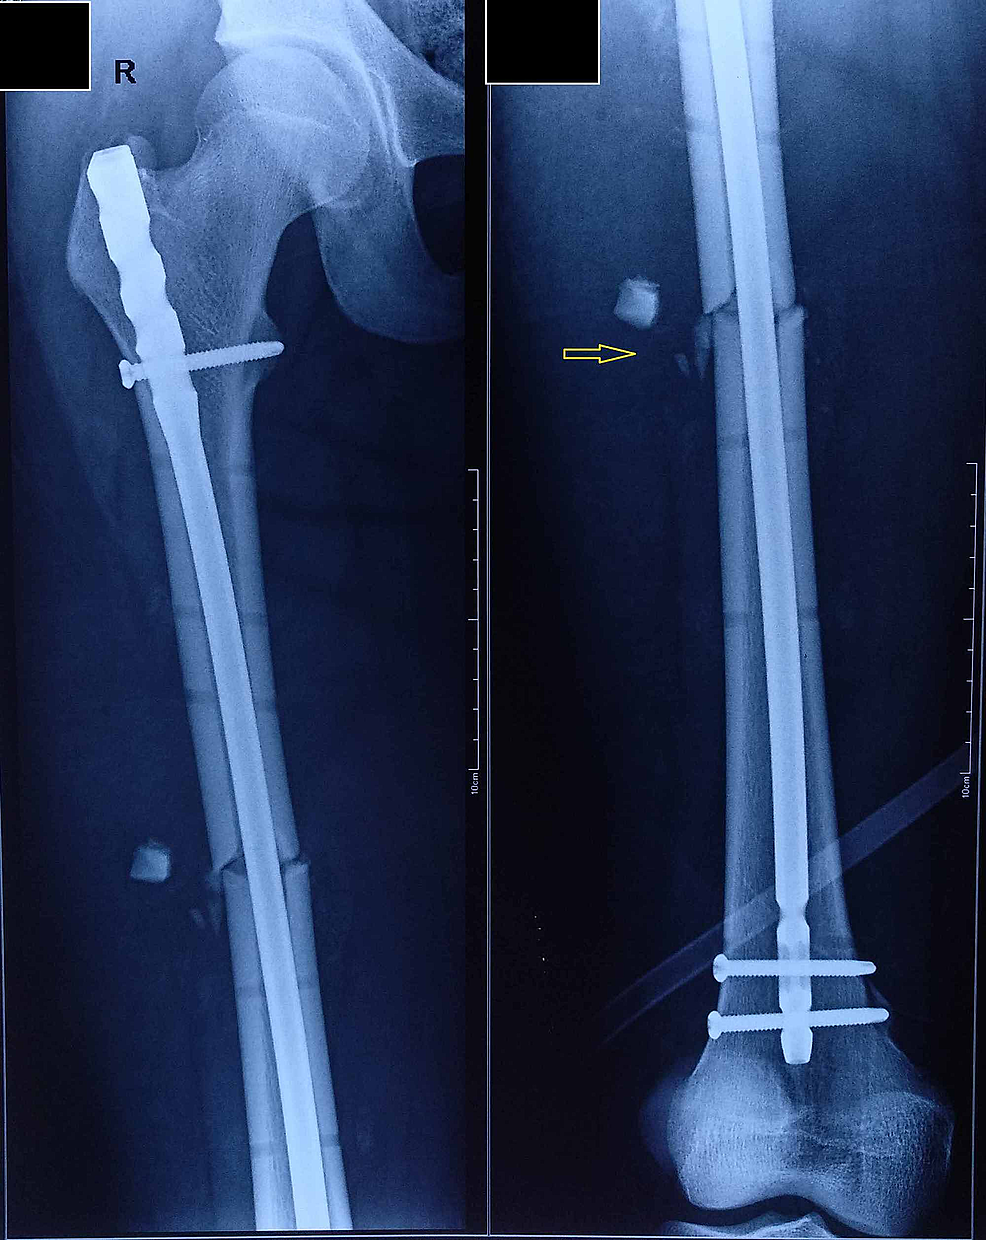

The Complication of a Retained Broken Distal Interlocking Screw Within Interlocking Screws Intramedullary Nail Placing distal locking screws into an intramedullary nail can be a difficult step for the young surgeon to master. Modern im nails permit placement of locking screws through bone and nail, to improve fixation both proximally and distally. These screws also serve to increase construct stiffness; Locked nails permit stable fixation which controls. A distal locking screw of the intramedullary. Interlocking Screws Intramedullary Nail.